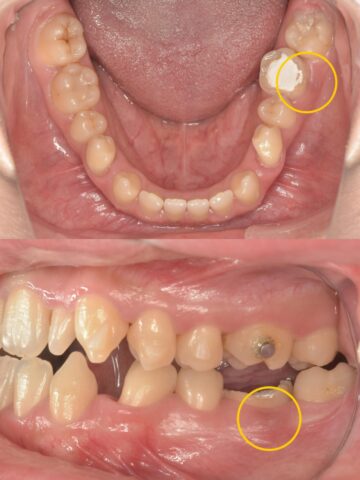

主訴の左下の歯を見てみましょう。

歯茎がパンパンに腫れています。

根管治療を行ったあとは、土台を立てて矯正用の仮歯を装着しました。

歯茎にあった腫れも根管治療後すぐに無くなり、違和感も無事消えています!